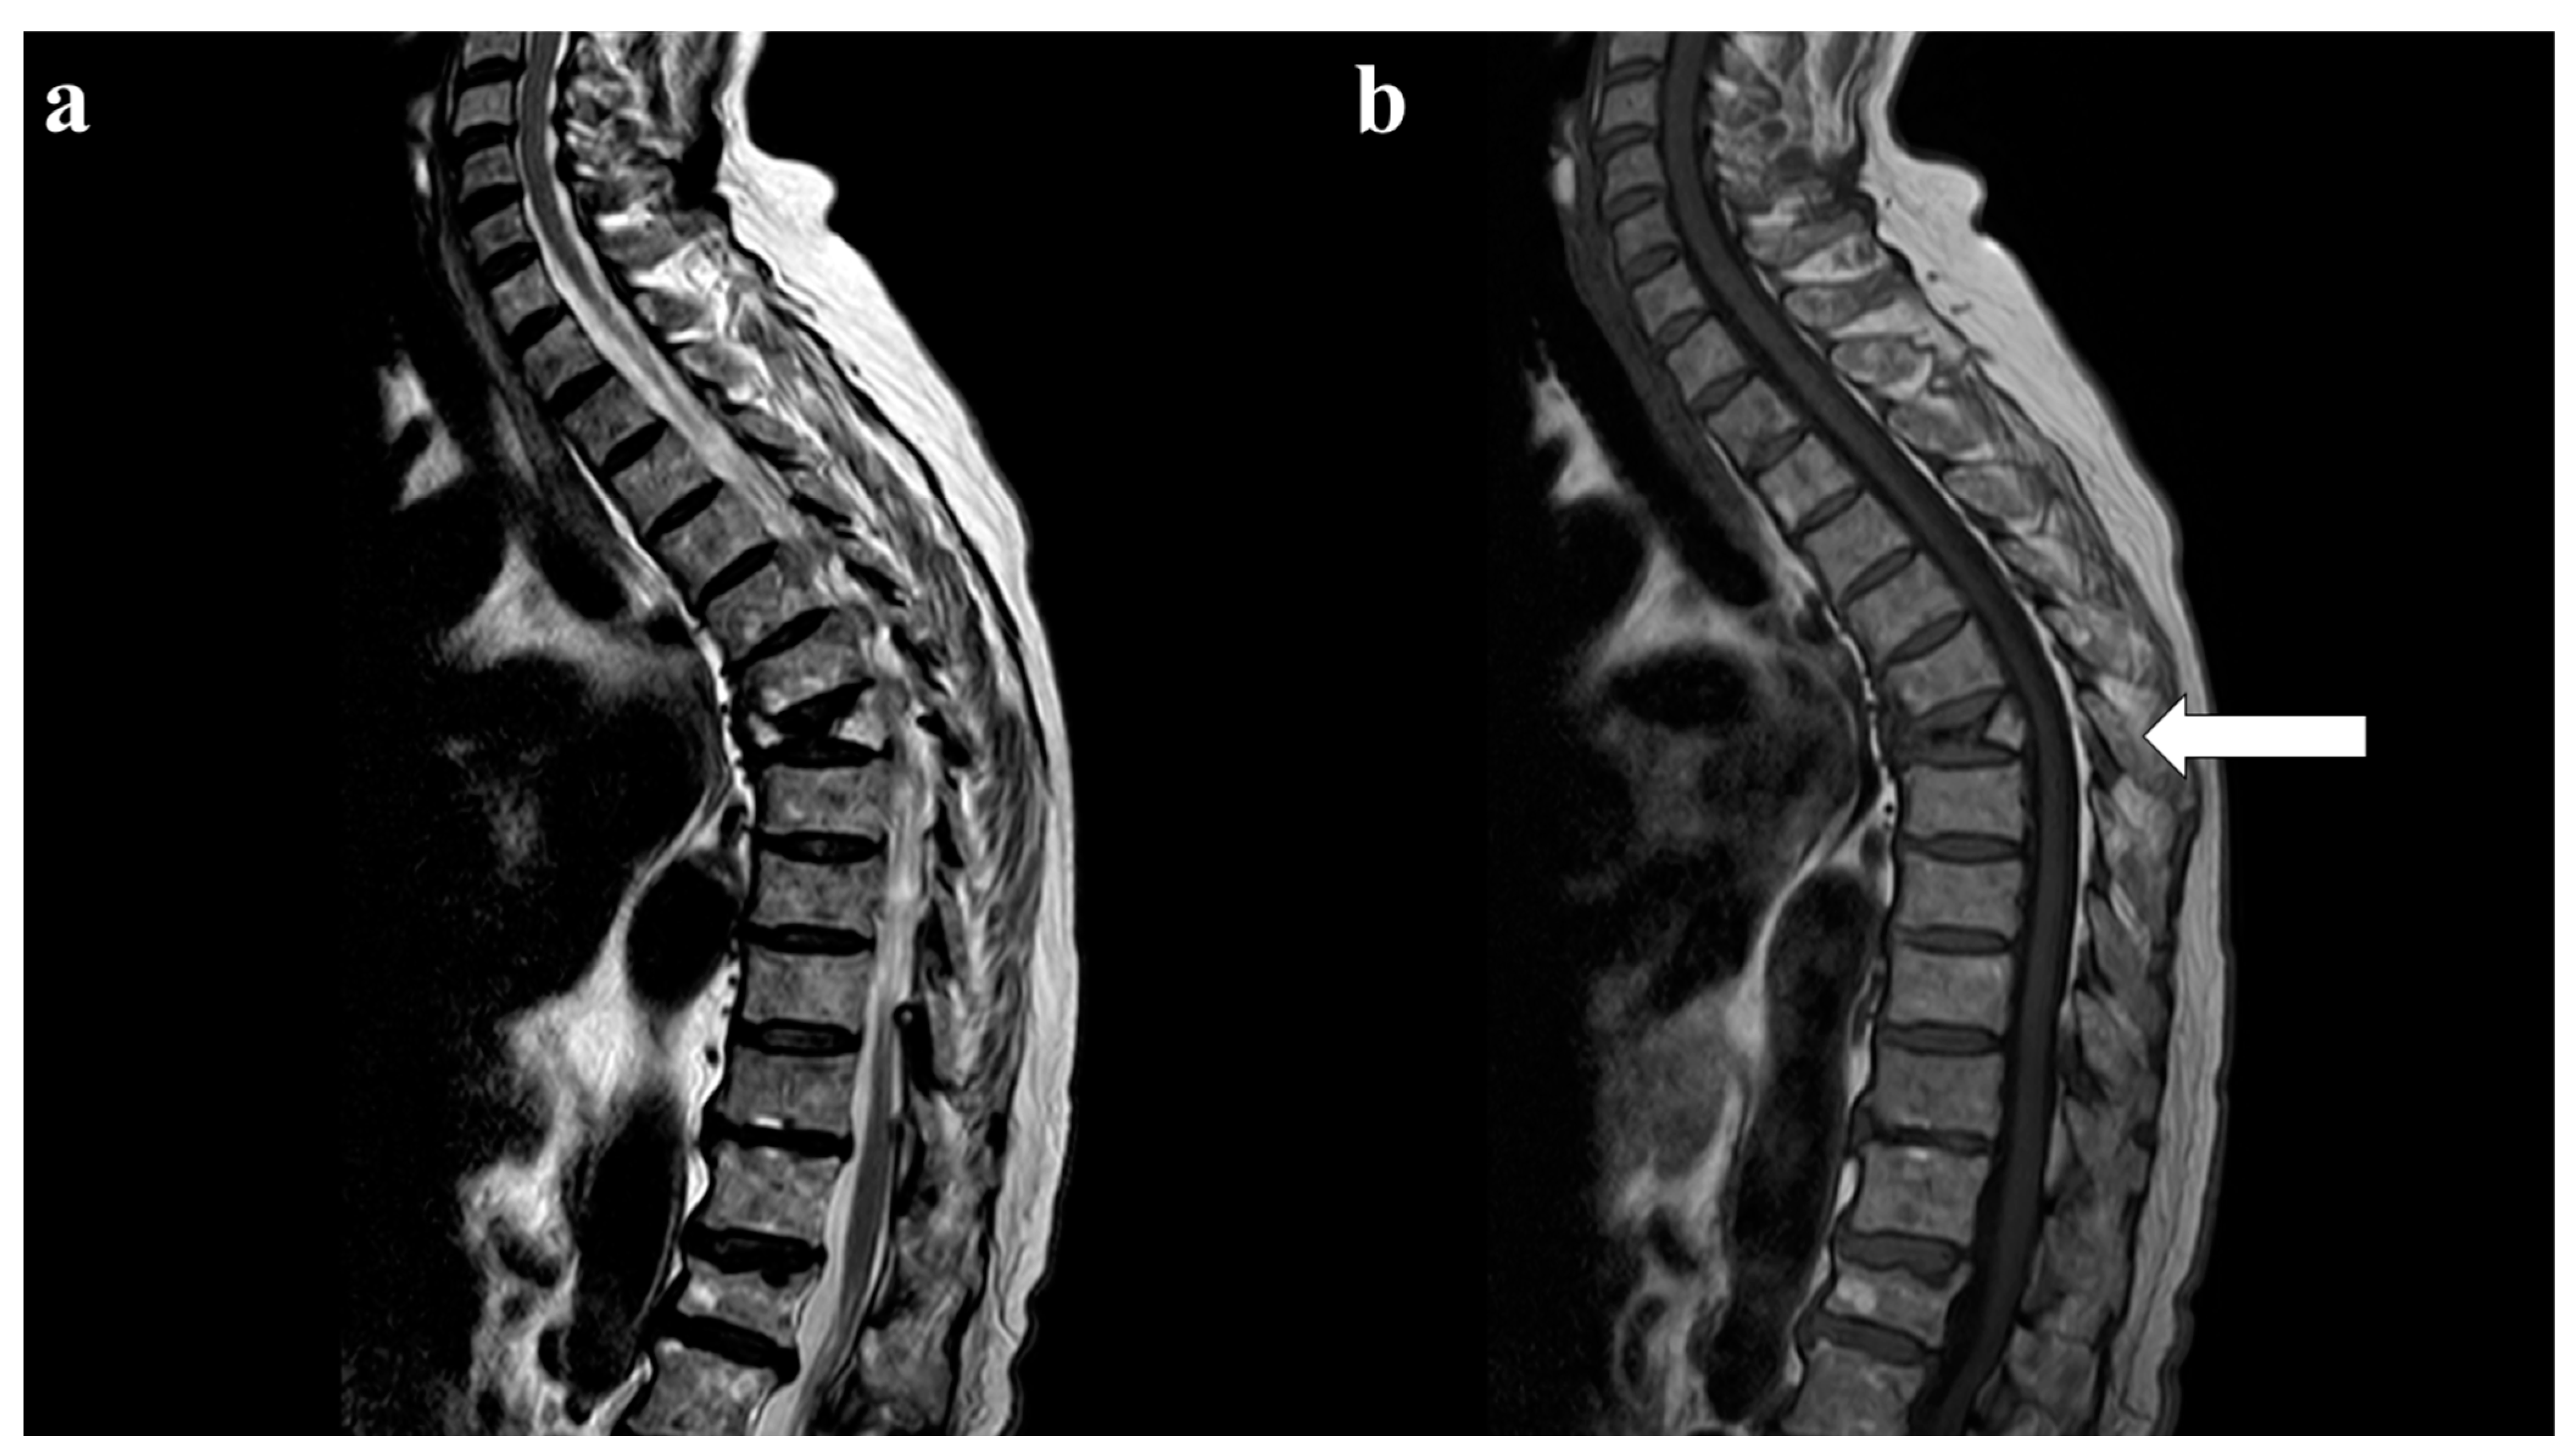

12. Chronic Recurrent Multifocal Osteomyelitis

- Falip, C.; Alison, M.; Boutry, N.; Job-Deslandre, C.; Cotten, A.; Azoulay, R.; Adamsbaum, C. Chronic recurrent multifocal osteo- my-elitis (CRMO): A longitudinal case series review. Pediatr Radiol. 2013, 43, 355–375. [Google Scholar] [CrossRef] [PubMed]

- Anderson SEHeini, P.; Sauvain, M.J.; Stauffer, E.; Geiger, L.; Johnston, J.O.; Roggo, A.; Kalbermatten, D.; Steinbach, L.S. Imaging of chronic recurrent multifocal osteomyelitis of childhood first presenting with isolated primary spinal involvement. Skeletal Radiol. 2003, 32, 328–336. [Google Scholar] [CrossRef] [PubMed]

- von Kalle, T.; Heim, N.; Hospach, T.; Langendörfer, M.; Winkler, P.; Stuber, T. Typical Patterns of Bone Involvement in Whole-Body MRI of Patients with Chronic Recurrent Multifocal Osteomyelitis (CRMO). Rofo 2013, 185, 655–661. [Google Scholar] [CrossRef]